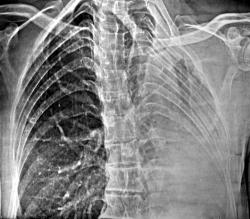

Неделю назад на фоне полного благополучия появилась одышка. Произведена обзорная ЭРГ. Заподозрен опухолевый ателектаз левого легкого. Ваше мнение?

Да, хорошо виден ателектаз левого лёгкого, компенсаторное расширение правого лёгкого, смещение органов средостения влево. Прекрасно виден "лизис" ребер слева.

Более крупным планом деструкция ребер слева.

Возможно, этот кругляшок, можно рассматривать, как "бластический" метастаз.

Возможно "это" можно рассматривать, как литические метастазы, возможно, как наложение гиперпневматизированного правого лёгкого. Конечно, при наличии "боковой" вопрос был-бы снят.

На фоне "воздушного столба" в проксимальной части левого главного бронха, почти на уровне бифуркации определяется "дополнительная тень". Классическая культя не определяется.

Представил как классику рентгеновской картны центрального рака.

Все может быть (по поводу ребер и пуговизы), но, по большому счету - "классика центрального рака" представлена.